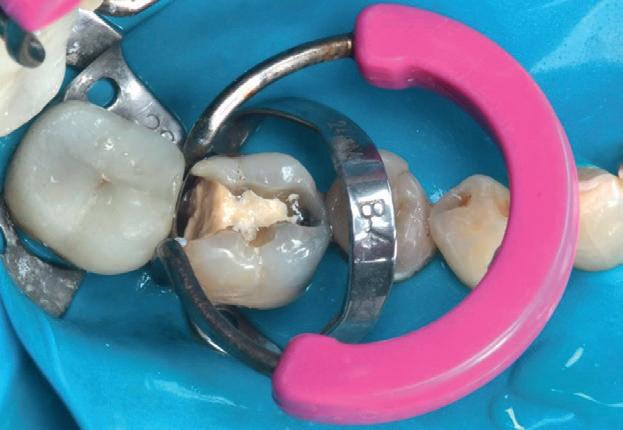

Planul de tratament a început cu accent pe restabilirea sănătății parodontale. Într-o ședință ulterioară, odată cu îmbunătățirea stării parodonțiului, s-a efectuat restaurarea molarului nr. 46. Sub anestezie la Spina Spix pe partea dreaptă și

Figurile:

3. Cavitate de clasa a II-a preparată.

4. Septomatrix pe poziție.

5. Cavitatea profundă.

izolarea cu digă de cauciuc, restaurarea din amalgam a fost îndepărtată complet și s-a obținut accesul la cavitatea carioasă (fig. 3-5). În ciuda proximității față de țesutul pulpar, nu a avut loc nicio expunere, iar cavitatea de clasa a II-a a fost restaurată complet cu Biodentine™ (fig. 6-8).